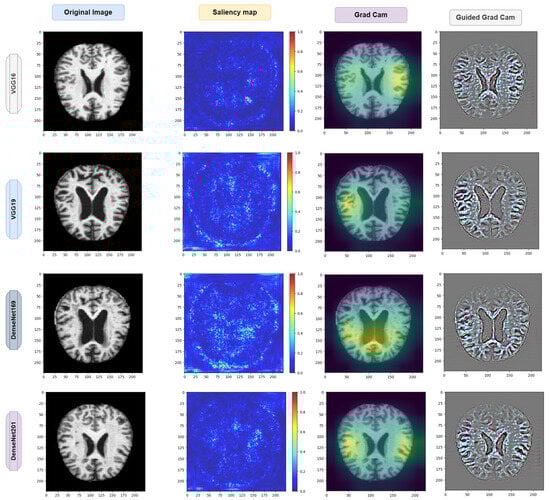

4.7. Exploring Saliency Maps and Grad-CAM

As previously mentioned in Section 3.9 and Section 3.10, the relevant studies have focused on computational techniques such as saliency maps and grad-CAM. These techniques serve as analytical tools that estimate the significance of each pixel solely by traversing through the network.

The underlying concept of this approach lies in identifying pixels that have a substantial impact on the node corresponding to the input image. If altering the values of a particular pixel leads to a noticeable change in that node, it is considered significant. Conversely, pixels with gradients close to zero are deemed unimportant, as their fluctuations do not affect the output node associated with the input images. Aggregate analysis across channels is employed to determine the collective relevance of the pixels rather than assessing the importance of each pixel channel in isolation.

For Alzheimers disease classification, we used saliency maps and grad-CAM. A saliency map and grad-cam can be used in a similar way as in occlusion experiments; they aid users in recognizing illness symptoms. In addition, this approach lacks sensitivity to the scattered critical areas since pixel importance is determined analytically rather than through occluding pixels.

However, when calculating a gradient analytically, only one backward pass is required to calculate all derivatives with respect to all pixels.

The saliency map and grad-CAM are capable of accurately locating the diseased areas within the supplied AD image. Good examples of how the visualization of saliency maps precisely marked the infected sections of leaves are shown in Figure 21 and Figure 22. Furthermore, the two distributed AD mold disease patches are localized, whereas the occlusion trials only reveal one diseased zone. Even with these encouraging outcomes, saliency maps frequently have noisy activations and lack clarity, which can be frustrating to users. For instance, in addition to the infected locations, the visualizations can display numerous activated regions. We have gone through several processes of saliency mapping operations, where some images are taken as input and are used to visualize the images, as was the case for the model we used throughout our paper. We used all the models represented in Figure 21 and Figure 22 to explore the maps. As mentioned earlier in Table 4, the models acquired some accuracy, and we tried to visualize the accurate combination and how the images behave when it is time to predict using saliency maps and gard-cam. It seems the edges are correctly identified, and there are some yellow dots in the saliency maps, as well as when there are two competing factors in the image; this is helpful. With these areas hidden, we can create a “counterfactual” image that should increase confidence in the first prediction. By combining this with guided backpropagation, which zeroes the gradient parts that have a detrimental impact on choice, the grad-CAM output can be further enhanced. This method more accurately reflects producing a high-resolution map with the same resolution as the input image using the guided backpropagation methodology. The high-resolution map is then masked using the grad-CAM heatmap to concentrate solely on the details that contributed to the prediction outcome.

Figure 21.

Visual depiction of the saliency map and grad-CAM results for the pretrained model.

Figure 22.

Visual depiction of the saliency map and grad-CAM results for the ensemble and proposed model.

Interpretability Using XAI Methods: The integration of saliency maps and grad-CAM in the proposed model enhances its interpretability and transparency in Alzheimer’s diagnosis. These XAI techniques provide valuable insights into the neural regions influencing diagnostic decisions, aiding clinicians and researchers in understanding the underlying mechanisms driving classification outcomes. By visualizing the regions of interest identified by the model, clinicians can gain confidence in its diagnostic recommendations and explore the potential biomarkers associated with Alzheimer’s disease pathology.